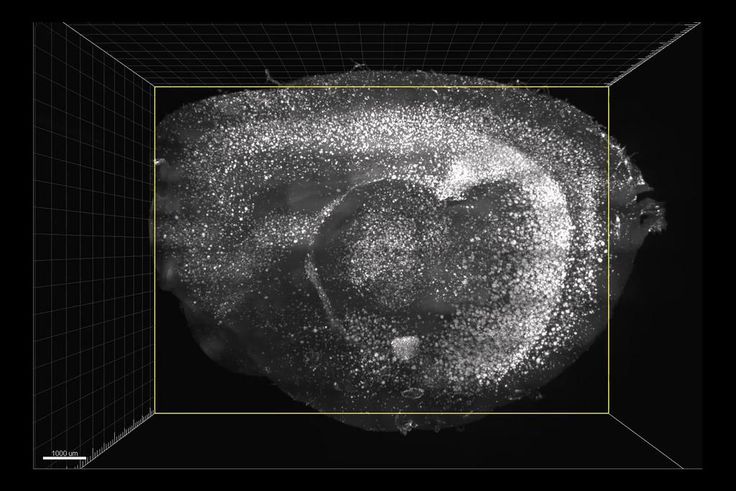

Uganda New York Times world 14.03.2019 Flashing Lights and Sounds Improve Memory and Learning Skills in Mice